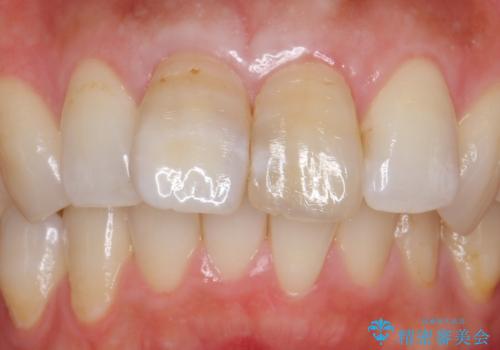

変色した歯を綺麗にしたい 根管治療からジルコニアクラウンでの修復

- 前歯の変色を主訴に来院されました。

変色に対してはかぶせ物で周囲の歯との色調を合わせます。

根管治療についてご説明をし、右上の1本だけ再根管治療を行うこととなりました。

先端に透明感のあるかぶせ物を装着することで審美的な問題を解決しつつ、少しガタついていた歯並びも改善することができました。